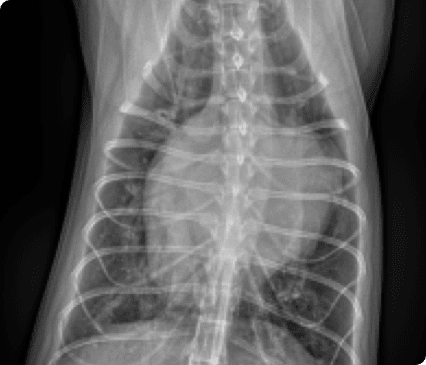

대학병원급 영상장비와 내과·외과 협진 시스템을 갖추고 있으며, 초기 무증상부터 중증 질환까지 체계적이고 종합적인 관리가 가능합니다.

일산시티동물의료센터는 최신 고해상도 초음파 장비를 통해 세밀하게 심장을 정밀하게 분석하여 심장질환을 진단합니다.